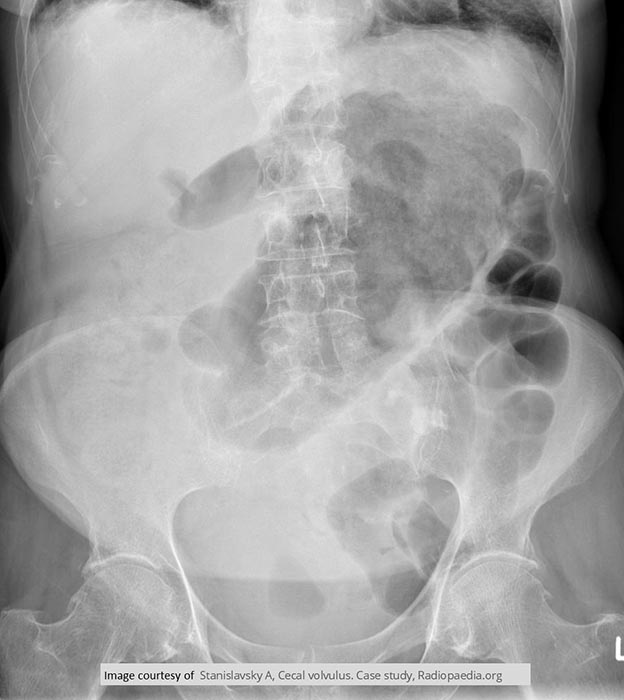

Where does volvulus most commonly occur?

In the cecum and sigmoid colon. (image shows cecal volvulvus)

How does cecal volvulus occur?

The cecum twists on its long axis and often displaces upward and to the left.

How is volvulus treated?

Emergency surgery to untwist the bowel.

When is bowel resection required in volvulus?

If the bowel has become necrotic.